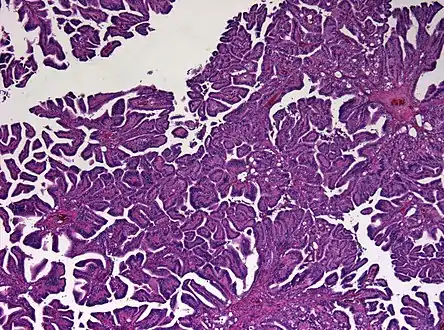

Micrograph of a choroid plexus papilloma. H&E stain.

Plexuspapillom Overview